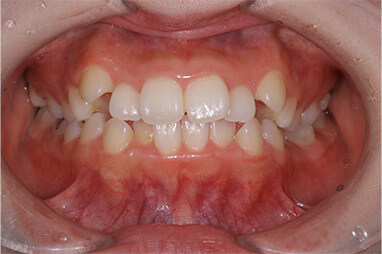

事故により上の前歯がなくなってしまいました。そのままインプラントをするのではなく、矯正治療により歯並びの改善をすることが、インプラントの予後を改善するポイントです。噛み合わせが悪いままインプラントをするとインプラントが後々トラブルを起こすことがあります。

インビザラインによる矯正治療後にインプラント治療を行い、治療終了。先天欠損であった右下の前歯は接着ブリッジによる治療を行いました。

抜歯に伴う骨欠損が大きい場合は、大規模な骨増生が必要になることがあります。